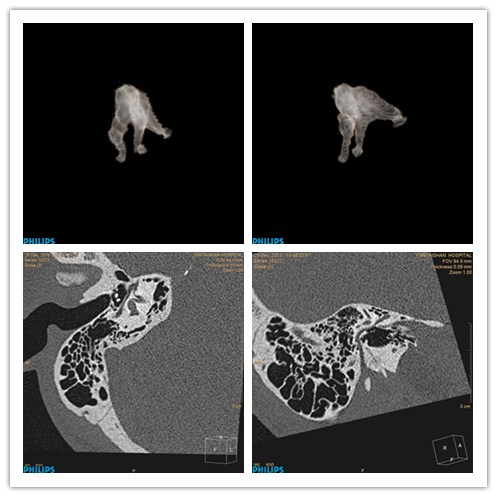

现如今,听力下降的患者越来越多,中耳炎、听小骨损伤、面神经管病变、耳蜗病等各种疾病都在影响着人们的听力健康。随着医学影像学技术的不断发展,可以显示精细骨性结构的高分辨率CT逐渐成为中内耳检查的首选方法。

近日,我院CT.MR室在张国伟主任的带领下,利用128层螺旋CT摸索出一套能够清晰显示内耳诸结构的新技术。利用我院的128层高分辨率CT,最薄层厚可达到0.67mm,能够满足内耳各结构重建后处理的要求。重组后可以清晰显示中内耳各个骨性结构形态,对听小骨、半规管、耳蜗及面神经管的显示均非常清晰。该技术可以了解到病变有无涉及到听小骨、半规管、耳蜗及面神经管,还可以用于术前导航,术后随访,人工耳蜗植入术的评估等。